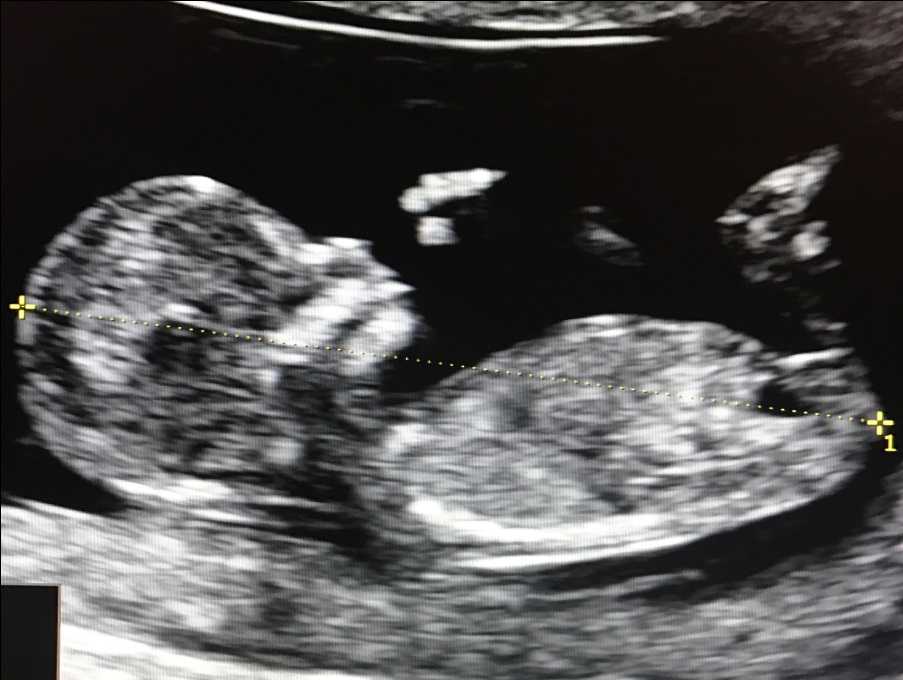

1. Копчико-теменной размер (КТР) плода

Этот показатель точно определяет срок гестации (беременности), особенно в случае, если женщина не помнит 1-й день последней менструации, либо если менструальный цикл у нее не регулярный. В заключении срок беременности выставляется по КТР плода, а не по дате последней менструации.

Правильное измерение КТР плода